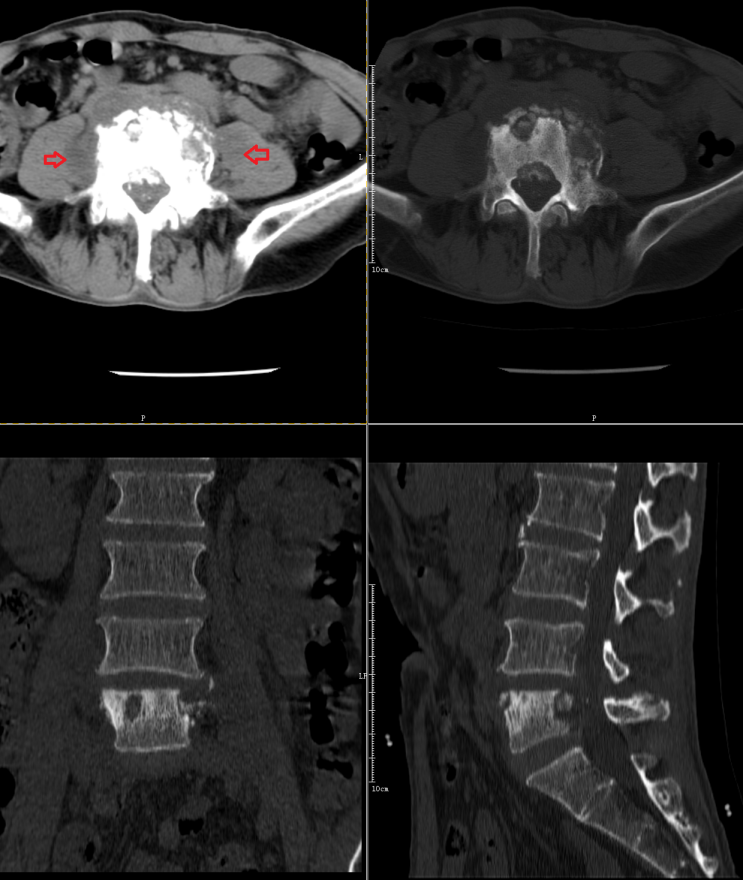

腰椎结核:表现为椎间盘及椎体骨质的破坏, 椎旁有时还伴有冷脓肿形成;

L4、5椎体结核伴椎旁脓肿形成。

转移瘤:有肿瘤病史,病变很少累及椎间盘,多个椎体溶骨性或膨胀性破坏,肿瘤易侵犯附件、椎管或椎旁。

MRI示 部分椎体及附件信号异常,T1WI及T2WI呈低信号,STIR序列呈明显高信号,DWI序列呈高信号。考虑为转移瘤。